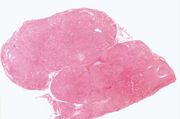

| 21:42, 20 August 2013 | IPLab6MM1.jpg (file) | 62 KB | This is a low-power photomicrograph of the mediastinal mass. The mass is encapsulated and contains cellular areas (blue) and areas of pale red material. | 1 | |